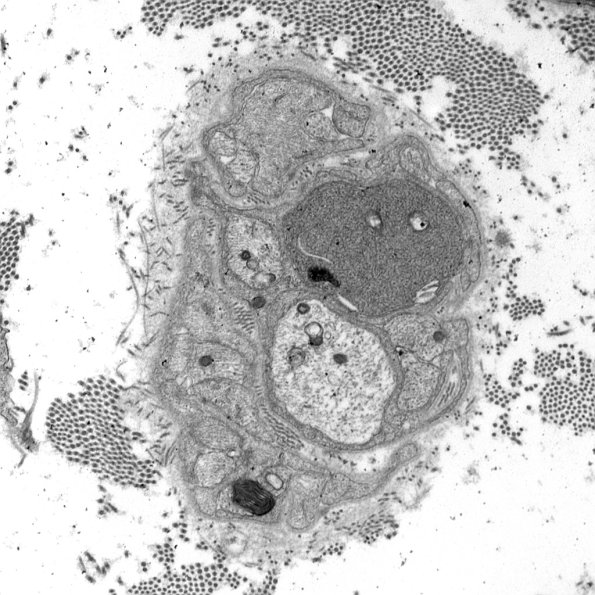

1B2A,B A similar appearance with dense axoplasm, tubulovesicular elements and clefts. (electron micrographs)